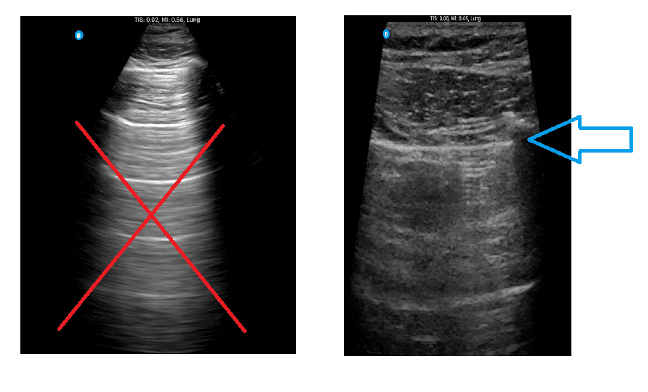

Figure 3. Optimizing Depth for Pneumothorax Evaluation

The image on the left shows a depth that is too deep for pneumothorax assessment, suitable for other lung imaging protocols, but not for this purpose. The image on the right demonstrates the ideal depth for evaluating lung sliding and the pleural line.